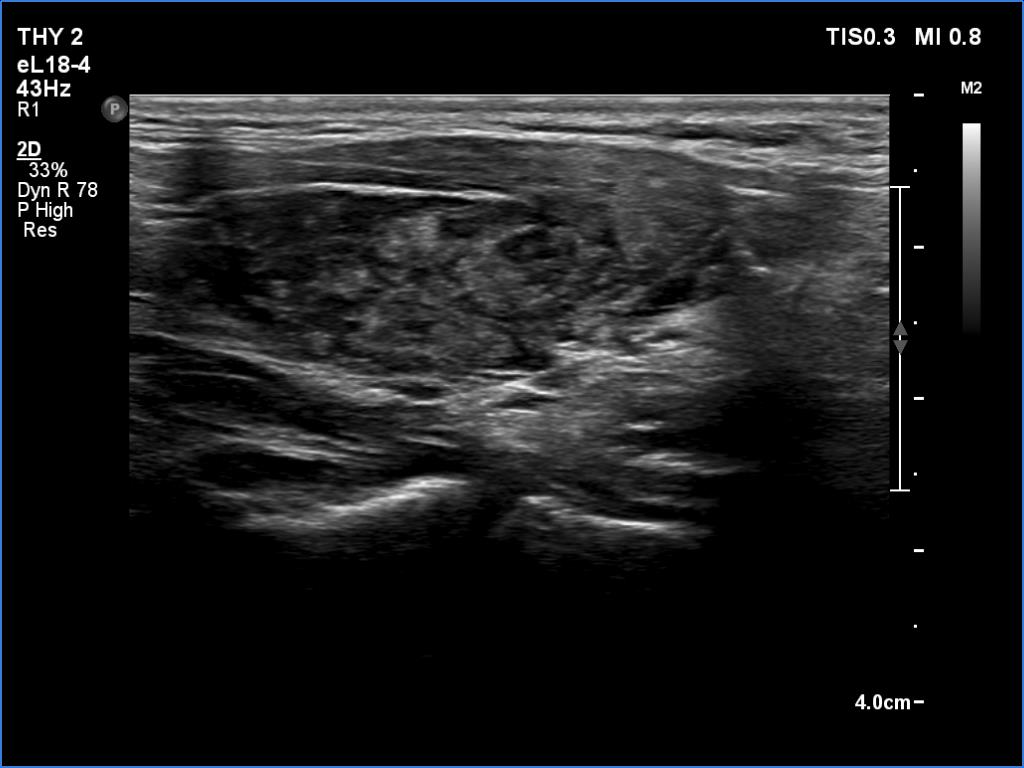

Ultrasonography. The thyroid was deeply hypoechoic and had numerous discrete iso/hyperechoic lesions. The latter had irregular shape and borders. The vascularity was increased. None of the discrete lesions corresponded to pathological nodules.